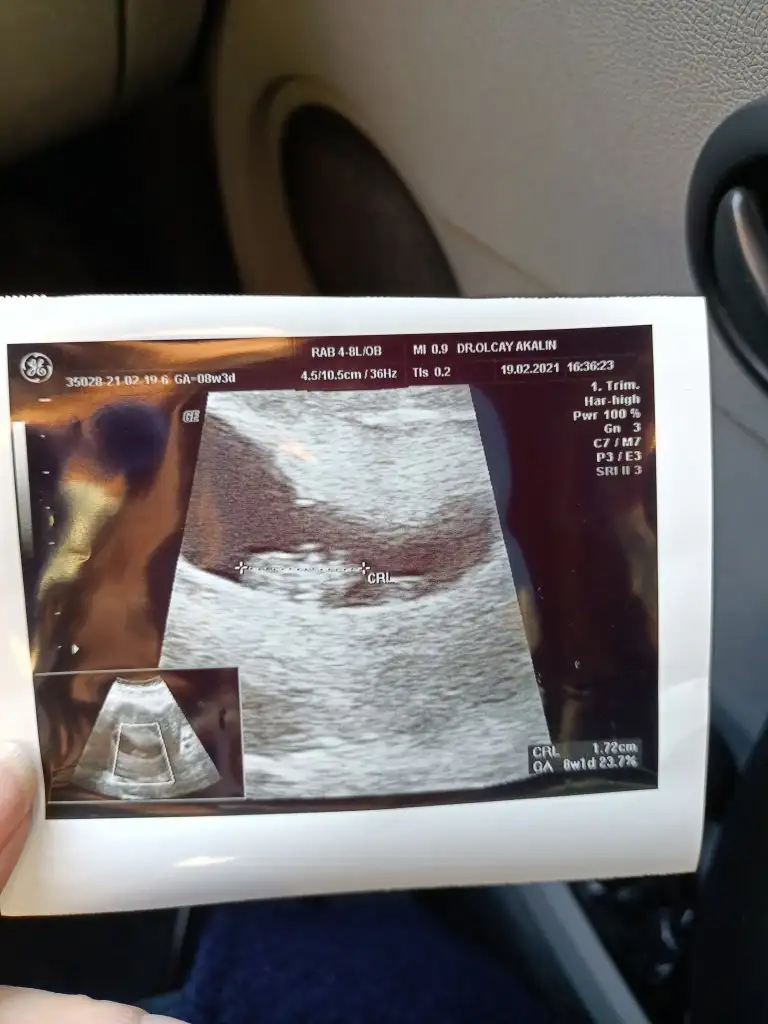

Merhaba bnmde burda 6+2 şuan 9+3 haftalığım çok merak ediyorum bir kızım var bunun cinsiyeti ne olucak diye lütfen bana da söylermisiniz tahmininizi ben hiç anlayamıyorum ☺️

Teoriye gore erkek gorunuyo bakalim.dogru cikicakmi sizin cinsiyeti ogrenmenize daha az zaman var ogrenince yazarmisiniz banada bende cok merak ediyorum dogruluk payini